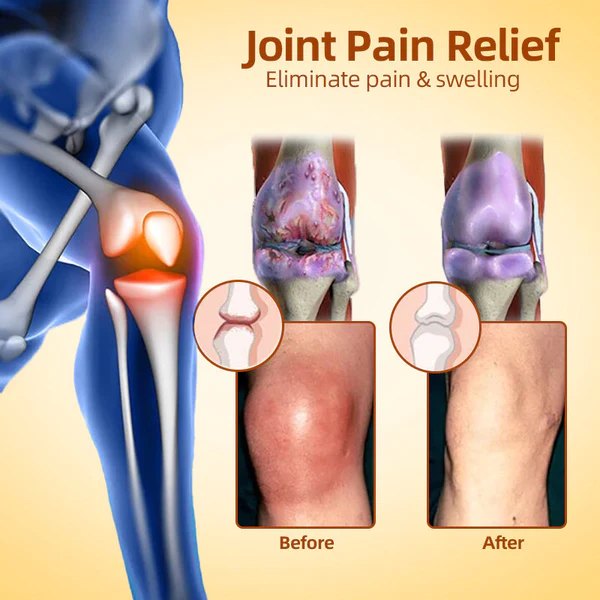

Cvreoz™ Cream effectively treats a wide range of joint problems. including osteoarthritis. rheumatoid arthritis. bursitis. tendonitis. osteoporosis. gout. carpal tunnel syndrome. ligament strains and sprains. thumb deformities. and tennis elbow. among other.

- Relieve Arthritis Pain

- Eliminate joint inflammation

- Eliminates cysts and edema

- Promotes joint tissue repair

- Improve joint elasticity and mobility

- Promotes joint repair and regeneration